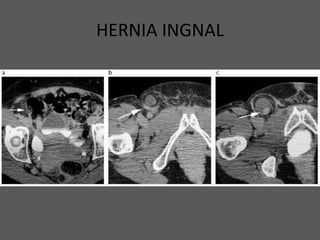

HERNIA INGNAL